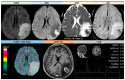

Primary Angiitis of the Central Nervous System (PACNS) is a rare disease and its diagnosis is a challenge for several reasons, including the lack of specificity of the main findings highlighted in the current diagnostic criteria. Among the neuroimaging pattern of PACNS, a tumefactive form (t-PACNS) is a rare subtype and its differential diagnosis mainly relies on neuroimaging. Tumor-like mass lesions in the brain are a heterogeneous category including tumors (in particular, primary brain tumors such as glial tumors and lymphoma), inflammatory (e.g., t-PACNS, tumefactive demyelinating lesions, and neurosarcoidosis), and infectious diseases (e.g., neurotoxoplasmosis). In this review, the main features of t-PACNS are addressed and the main differential diagnoses from a neuroimaging perspective (mainly Magnetic Resonance Imaging-MRI-techniques) are described, including conventional and advanced MRI.